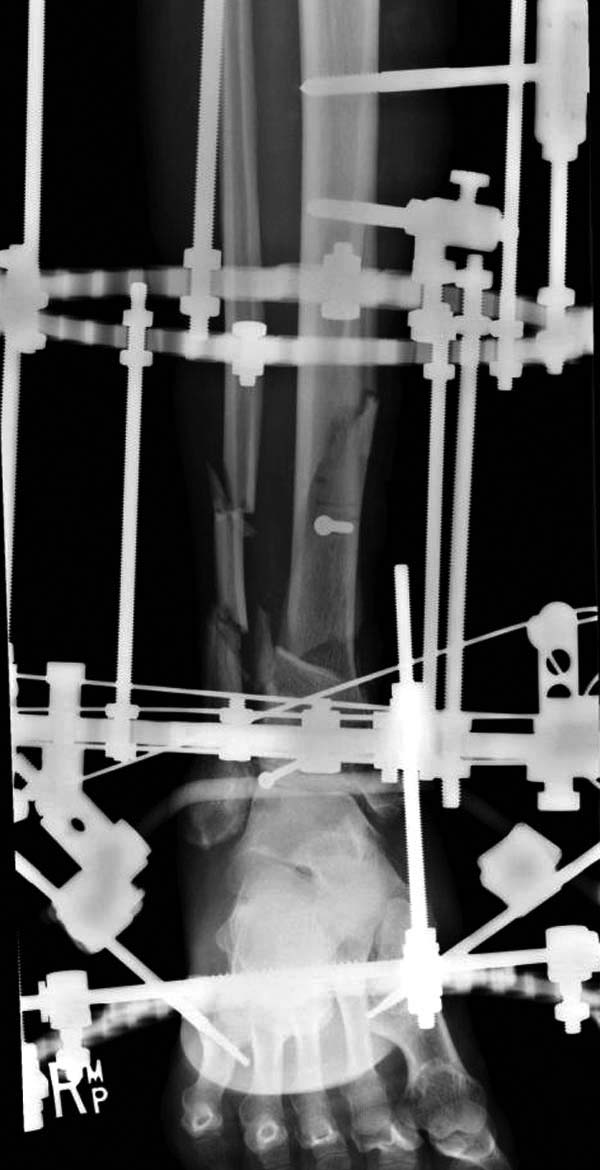

После спадения отека вариантов фиксации много, включая мининвазивную технику, но данный случай закончили установкой простого аппарата Илизарова.

Через три дня оперирована стопа и для нейтрализации сил колонн оставили наружный фиксатор.